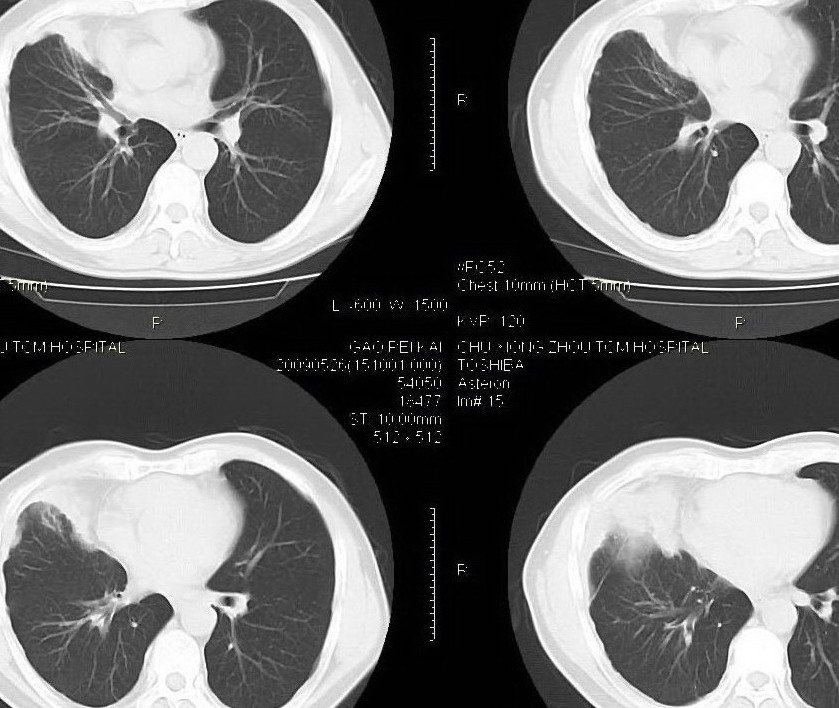

男,56岁,右侧腋窝下巨大软组织包块转移。欢迎讨论。

该病例为已经确诊的右侧恶性胸膜间皮瘤病例,有青石棉接触史,早期就是胸水,右侧胸壁“花边状改变”,心隔角区软组织阴影形成。近期右侧腋窝下巨大软组织包块,病检为转移瘤。图片没有完全考来,主要是给大家看一下胸膜间皮瘤的病例。,右侧

右侧腋窝下巨大软组织包块已经被切除后的ct片,该病例有多家医院较多的ct检查片。

1)右肺中叶节段性肺不张。2)右肺中叶肺癌不排除。3)右侧胸膜增厚。

右心膈角区一不规则肿块伴相邻胸膜不规则增厚,考虑胸膜间皮瘤(恶性)?右肺中叶内侧段肺癌?建议穿刺活检。